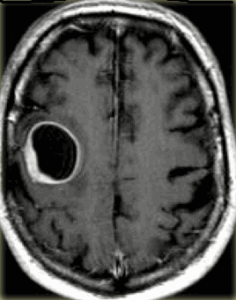

Глиобластома: симптомы, выявляемые с помощью МРТ. Аксиальный срез в режиме Т1 после контрастирования препаратом гадолиния демонстрирует распространенную опухоль правой лобной доли. Изображение предоставлено доктором George Jallo.

МРТ того же пациента. Т2-взвешенное изображение демонстрирует то же поражение, что и на предыдущем рисунке с заметным отеком и смещением срединных структур. Эти находки соответствуют высокой степени злокачественности опухоли.